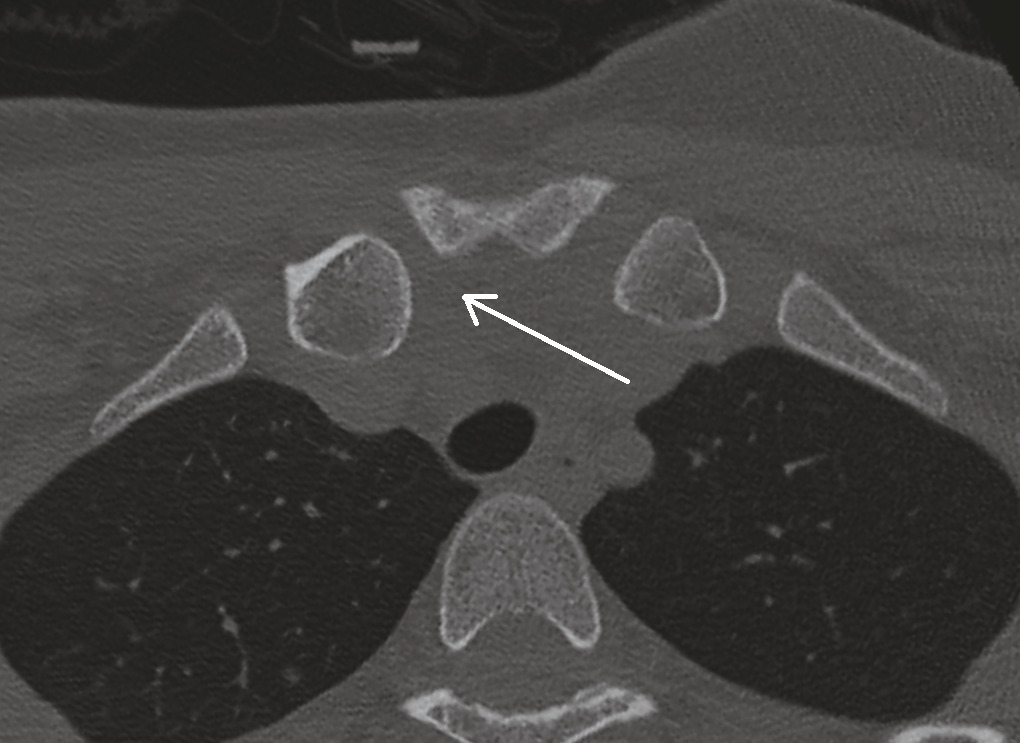

Ce dernier, réalisé deux semaines après le traumatisme, objective une subluxation postérieure de l’articulation sternoclaviculaire droite avec pincement relatif de l’interligne (fig. 2 ). Une réduction est donc réalisée.

Ce dernier, réalisé deux semaines après le traumatisme, objective une subluxation postérieure de l’articulation sternoclaviculaire droite avec pincement relatif de l’interligne (

La subluxation postérieure de l’articulation sternoclaviculaire est une forme mineure de luxation sternoclaviculaire postérieure. L’articulation sternoclaviculaire est très mobile dans tous les plans de l’espace, y compris en rotation. C’est une articulation très sollicitée, pour tout mouvement du membre supérieur.

Les subluxations sternoclaviculaires sont rares et souvent méconnues initialement (1 patient sur 3). Cliniquement, une douleur intense avec une imagerie radiologique standard peu contributive doit attirer l’attention. Les déformations locales peuvent être absentes (cas de cette patiente) et la luxation est souvent masquée par l’œdème et l’hématome. Tout patient ayant une douleur post-traumatique (EVA supérieure à 6) au niveau d’une articulation sternoclaviculaire devrait bénéficier d’une imagerie en coupe lors de sa prise en charge initiale. Les subluxations sternoclaviculaires surviennent le plus souvent à la suite de traumatismes indirects à haute énergie : chute sur une épaule antépulsée en rotation interne et, plus rarement, par choc direct. La proximité des gros vaisseaux et des poumons peut entraîner de graves complications chez les sujets jeunes qu’elles concernent plus particulièrement. De ce fait, toute luxation doit être réduite et sa stabilité évaluée. Les réductions, chirurgicales ou orthopédiques, doivent être réalisées au bloc opératoire. Il est plus prudent de faire appel à une équipe chirurgicale multidisciplinaire comprenant un chirurgien thoracique.